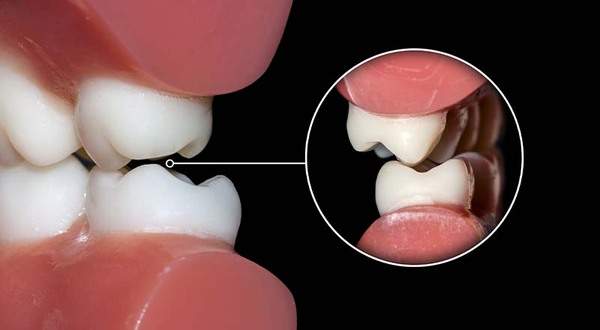

親知らずがあると歯が押される

親知らずが真横にはえていることで、手前の歯がおされてしまいます。押されることで、前歯の歯並びが変わってしまうこともあります。よく、若い時は歯並びが綺麗だったのに、歳を取ったら前歯の歯並びがガタガタしてきたというのは、親知らずが原因のことも多いです。